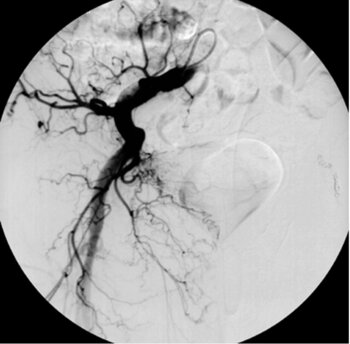

Digitale Subtraktionsangiografie: Superselektive Sondierung und Darstellung der mutliplen Blutungsherde. Die Leberarterien werden durch die zystischen Metastasen ausgespannt.

Digitale Subtraktionsangiografie: Nach Spiralembolisation mehrerer Subsegmentäste der A. hepatica stehen die zahlreichen Blutungen.